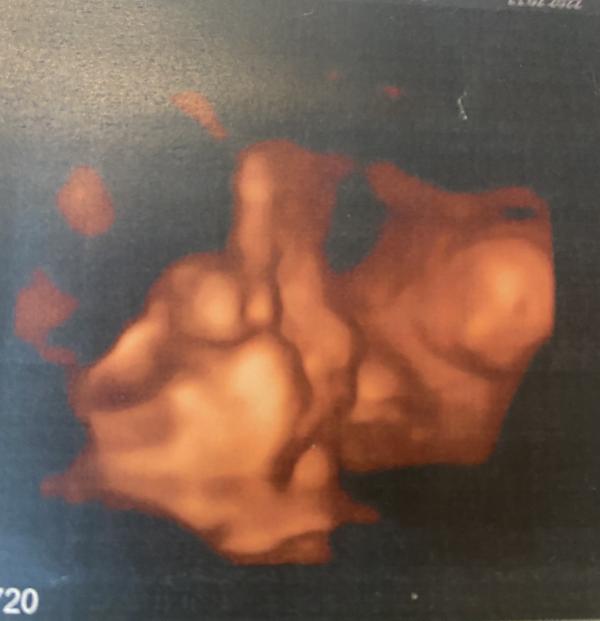

Сегодня с мужем ходили на узи😍Внепланово, чисто для себя)))Господи, сколько эмоций, сколько счастья❤️Наша малышка уже примерно 2 кг😘Наша радость, наше счастье как же мы тебя ждём❤️❤️❤️

Третий скрининг был в 5 жк, где я наблюдаюсь. Впечатлений ни каких, убитый кабинет, допотопная техника, не плохой доктор, но я мне даже ни одним глазом не дали взглянуть на малышку. А сегодня, просто решили с мужем сходить вместе на 3д узи пошли в медэксперт, остались очень довольны хороший доктор, все рассказала, все посмотрела, все показала)))